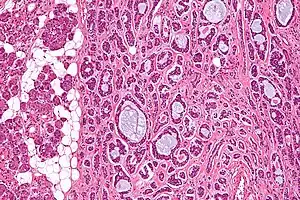

| Micrograph of an adenoid cystic carcinoma of a salivary gland (right of image): Normal serous glands, typical of the parotid gland, are also seen (left of image), H&E stain. | |

Adenoid cystic carcinoma is a rare type of cancer that can exist in many different body sites. This tumor most often occurs in the salivary glands, but it can also be found in many anatomic sites, including the breast,[1][2] lacrimal gland, lung, brain, Bartholin gland, trachea, and the paranasal sinuses.